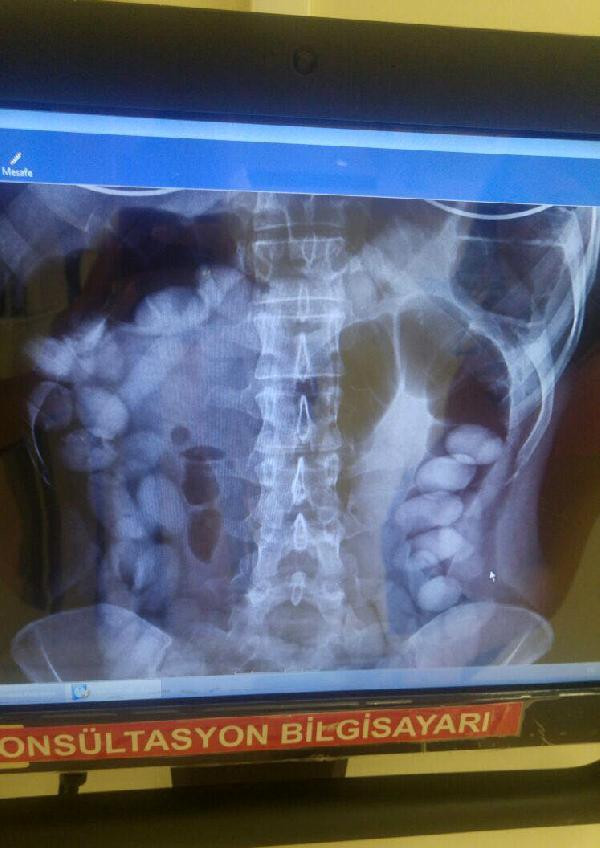

İSVİÇRE'nin Zürih kentinden uçakla Antalya'ya gelen Venezuela uyruklu 29 yaşındaki M.S.R. adlı kadının midesinde, her biri 10-12 gram ağırlığında 78 kokain kapsülü tespit edildi.

M.S.R., uçaktan indikten sonra gözaltına alındı. Yapılan iç muayenesinde, midesinde çok sayıda yabancı cisim olduğu görülen M.S.R., hastanede gözetim altına alındı. Kadının midesinde, her biri 10-12 gram ağırlığında 78 kokain kapsülü tespit edildi. Şu ana kadar 71 kapsülün doğal yollarla çıkartıldığı kaydedildi.